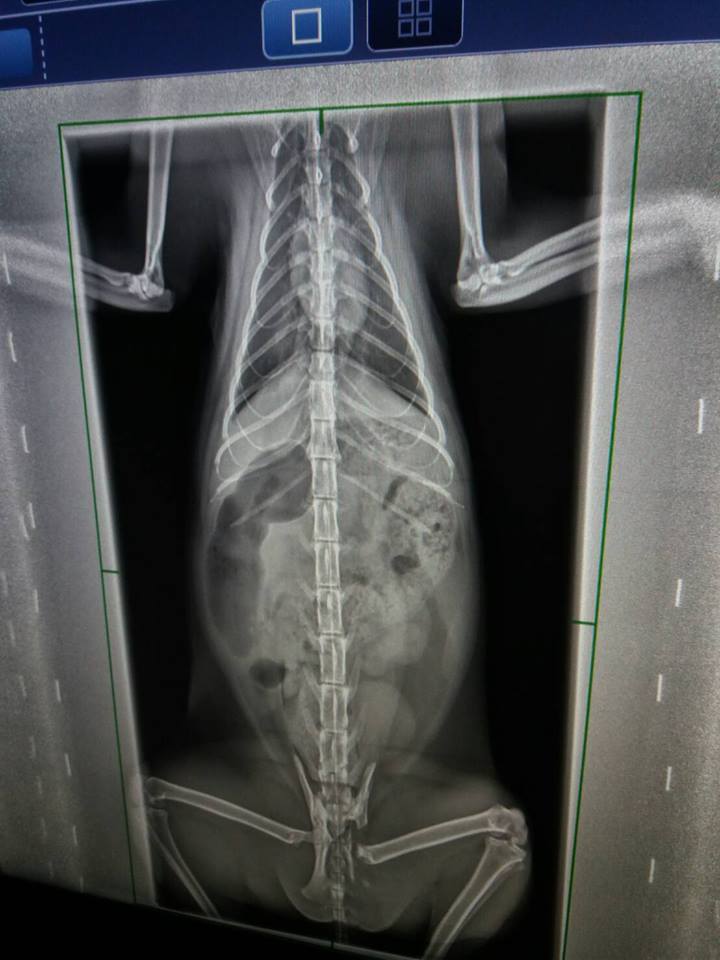

X光下發現大腸寬度變大,

認為有一可能導致艾咪雖有大便但無便意,等到積很久後,

後面大便已乾,